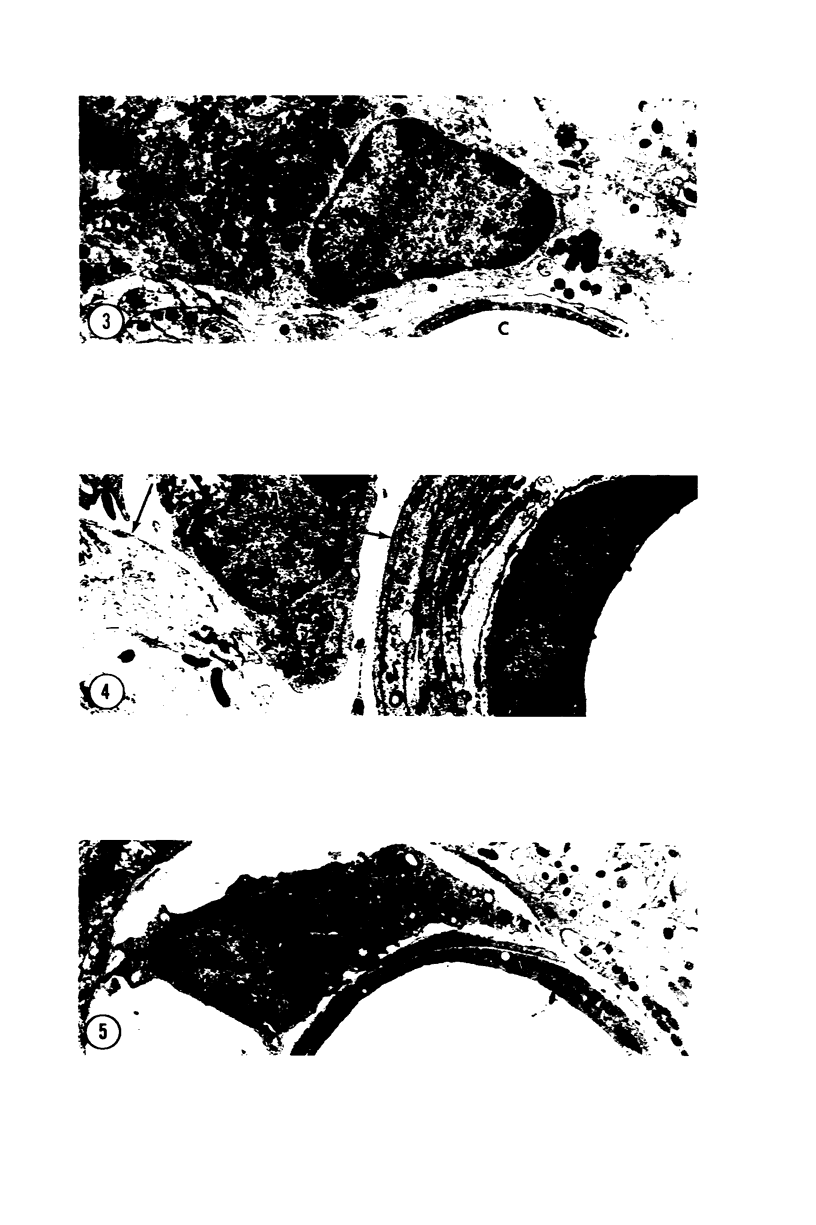

Forty-eight rats received intracerebral injections of sterile colloidal carbon. At intervals between 10 minutes and 31 days after carbon injection, the rats were perfused with glutaraldehyde, and autopsies were performed. Between 10 minutes and 3 hours after injection, carbon particles were extracellular and located strictly within the needle track. During the first few days the carbon was ingested by macrophages. Initially absent, carbon-laden macrophages spread to the neuropil immediately surrounding the injection site at 7 to 31 days following injection. These carbon-laden macrophages frequently were elongated within the neuropil and resembled microglia. Carbon-laden macrophages eventually accumulated around local vessels and in perivascular spaces. Many macrophages containing carbon remained in the injection site at the longest sampling interval of 31 days. Results indicate two macrophage responses to colloidal carbon in the central nervous system: a) an indolent population remains in the injection site for at least 1 month and b) a second population of macrophages emigrates through the neuropil. They eventually surround local vessels and enter the perivascular space. The migrating macrophages offer an explanation for the peculiar perivascular cells in Krabbe's disease and may provide a link between the CNS parenchyma and immunocompetent cells.